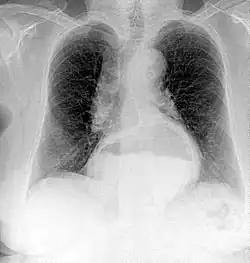

Projectional radiographs

Projectional radiography is the practice of producing two-dimensional images using X-ray radiation. Bones contain a high concentration of calcium, which, due to its relatively high atomic number, absorbs X-rays efficiently. This reduces the amount of X-rays reaching the detector in the shadow of the bones, making them clearly visible on the radiograph. The lungs and trapped gas also show up clearly because of lower absorption compared to tissue, while differences between tissue types are harder to see.[115]

Projectional radiographs are useful in the detection of pathology of the skeletal system as well as for detecting some disease processes in soft tissue. Some notable examples are the very common chest X-ray, which can be used to identify lung diseases such as pneumonia, lung cancer, or pulmonary edema, and the abdominal x-ray, which can detect bowel (or intestinal) obstruction, free air (from visceral perforations), and free fluid (in ascites). X-rays may also be used to detect pathology such as gallstones (which are rarely radiopaque) or kidney stones which are often (but not always) visible. Traditional plain X-rays are less useful in the imaging of soft tissues such as the brain or muscle. One area where projectional radiographs are used extensively is in evaluating how an orthopedic implant, such as a knee, hip or shoulder replacement, is situated in the body with respect to the surrounding bone. This can be assessed in two dimensions from plain radiographs, or it can be assessed in three dimensions if a technique called '2D to 3D registration' is used. This technique purportedly negates projection errors associated with evaluating implant position from plain radiographs.[116]